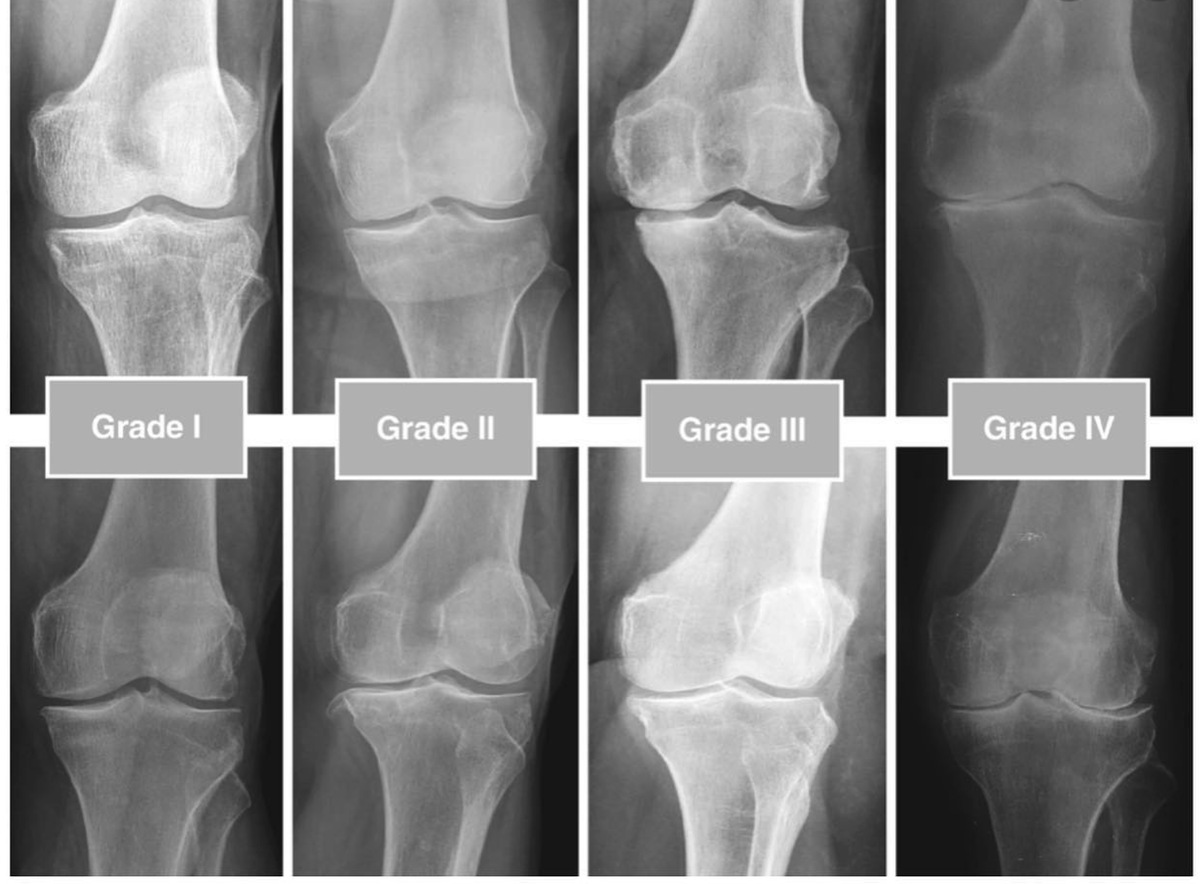

1. Артроз. Это не «отложение солей»! Это поэтапное стирание гиалиновых хрящей – того самого скользкого и прочного покрытия, которое должно служить вам до глубокой старости. При ожирении процесс запускается на 10-20-30 и даже 40 (!!!) лет раньше срока (в зависимости от возраста, когда появилось ожирение). На снимках мы видим сужение суставных щелей, краевые экзостозы (костные «шипы»), субхондральный склероз.

стадии артроза по Kellgren-Lawrence

Процесс разрушения хрящей называется хондромаляцией, на МРТ выделяют 4 степени (4 ст. — почти полное отсутствие хряща, когда кость начинает «тереться» о кость). Разрушение хрящей сопровождается болью, отеком костного мозга, скоплением жидкости в суставах.